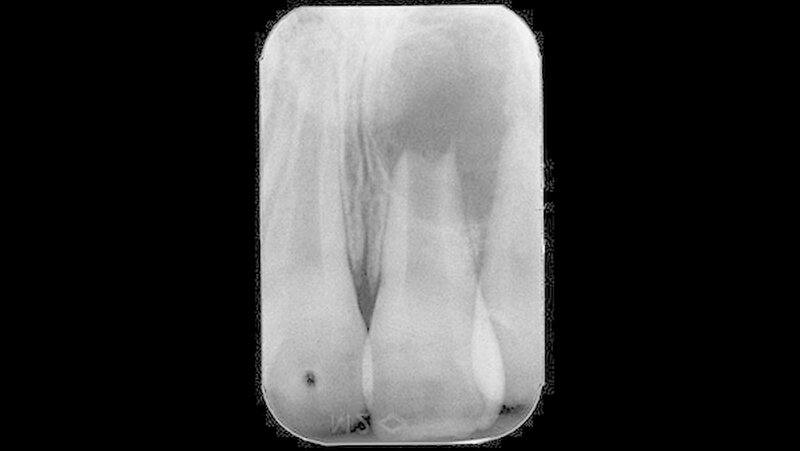

Zwei Jahre später bemerkte der Patient eine dezente Schwellung im Bereich der linken Oberlippe. Unter Schmerzen oder Aufbissempfindlichkeit litt der Patient dabei nicht. In diesem Zustand stellte sich der Patient in der Poliklinik für Zahnerhaltung des Universitätsklinikums Münster erstmals vor. Nach eingehender Anamnese und Befunderhebung wurde eine aktuelle Zahnfilmaufnahme angefertigt (Abbildung 2).

Auf der Zahnfilmaufnahme zeigte der Zahn 21 ein weiterhin nicht abgeschlossenes Wurzelwachstum und eine ausgedehnte apikale Osteolyse. Im Vergleich zur altersentsprechend entwickelten Wurzel des Zahnes 11 erschien die Wurzellänge des traumatisierten Zahnes verkürzt. Auch stellte sich das Lumen des Wurzelkanals im Seitenvergleich vergrößert dar.